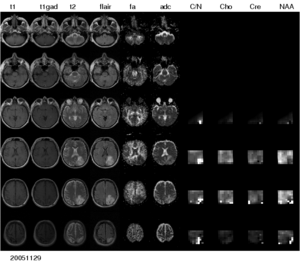

Figure 1: Multi-modal image data from a patient with low-grade glioma. A large number of different modalities and derived parameter volumes are acquired during the monitoring of tumor growth.

We are interested in developing computational methods for the assimilation of magnetic resonance image data into physiological models of glioma - the most frequent primary brain tumor - for a patient-adaptive modeling of tumor growth.

The project has three main aims: 1) the automated segmentation of tumors in large multi-modal image data sets to make information of different MR image modalities accessible for the tumor model, 2) the development of methods for the image-based estimation of parameters in reaction-diffusion type models of tumor growth, and 3) the processing and analysis of magnetic resonance spectroscopic images (MRSI) as a potential application of the tumor model.